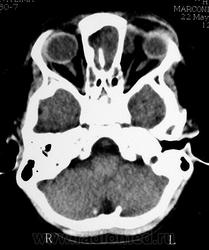

Орбитальная патология. Черепно-мозговые грыжи. +

Фронто-орбитальное энцефалоцеле